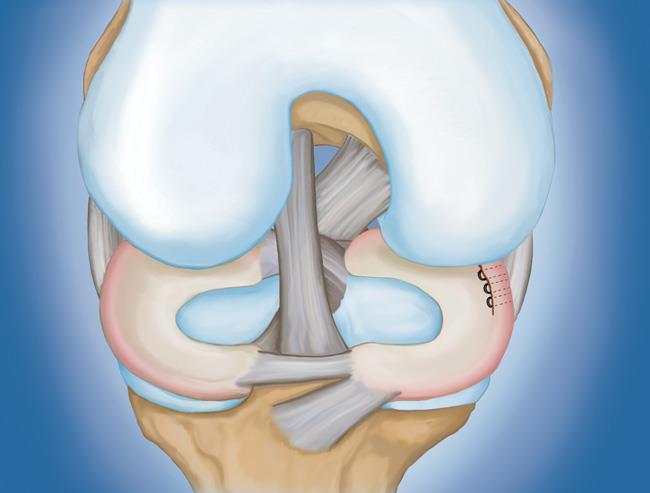

程序。 膝關節鏡檢查是最常進行的外科手術之一。在這個過程中,外科醫生通過膝蓋上的一個小切口(入口)插入一個微型相機。這提供了膝蓋內部的清晰視圖。然后外科醫生通過兩個或三個其他小入口插入手術器械以修剪或修復撕裂。

- 半月板修復。 一些半月板撕裂可以通過將撕裂的碎片縫合(縫合)在一起來修復。撕裂能否成功修復取決于撕裂的類型,以及受傷半月板的整體狀況。因為半月板必須一起愈合,修復的恢復時間比半月板切除術長。